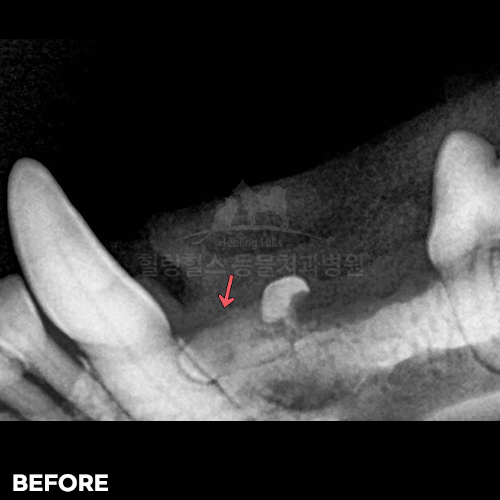

[강아지발치] 잇몸뼈가 녹은 구멍에 자기잇몸뼈가 튼튼하게 재생되어 채워졌어 - 강아지치아발치 2년 후 구강X-ray 비교! -